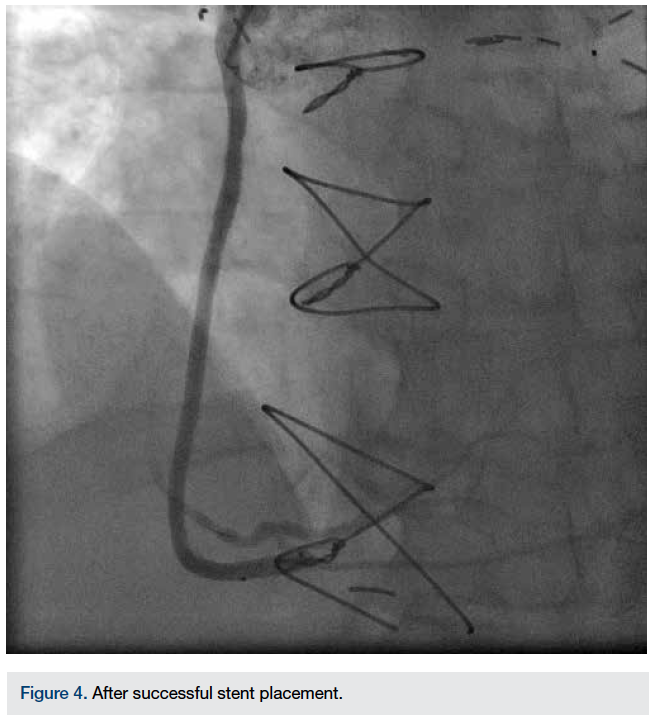

Right radial artery (RA) access was chosen for the procedure, as the patient did not have a left internal mammary artery (LIMA) graft. We routinely use the Seldinger technique (posterior wall puncture or through-and-through puncture) to obtain radial artery access. After the local anesthetic infiltration, a 20-gauge Teflon-coated Angiocath needle (B. Braun) was used to obtain access. Skin was entered at a 45-degree angle and after entering the anterior wall of the radial artery, a flash of blood was seen in the transparent hub of the Angiocath. At this point, the Angiocath was advanced further and the posterior wall was punctured. The stylet was removed and a 0.021-inch guide wire (supplied with the Terumo Glide Access Kit, Terumo Corporation) was placed in the hub of the Teflon cannula and the entire system was very gradually withdrawn. When the pulsatile flow was seen in the hub of the Teflon cannula, the guide wire was advanced. After advancing 2-3 inches, some resistance was felt. The wire then advanced about 6-7 inches further and at that point, there was significant resistance. To confirm the intraluminal course of the wire, the Teflon cannula was advanced over the wire into the RA. There was pulsatile flow, but not as brisk. An angiogram was performed by injecting diluted contrast through the Teflon cannula. The radial artery angiogram showed radial artery dissection (Figure 1).